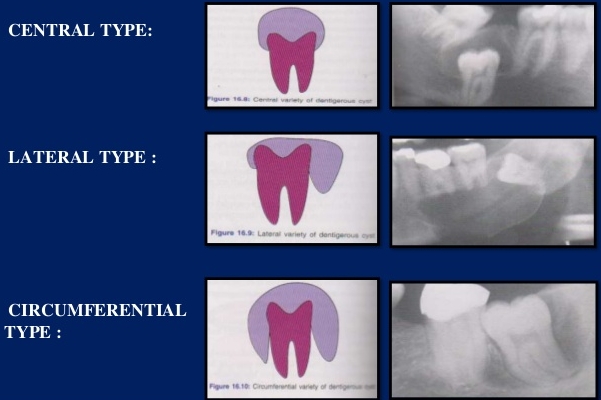

- The dental follicle may expand around the unerupted or impacted tooth in three variations : (a) circumferential (b) lateral (c) central or coronal

Radiographic features :

- generally reveals a unilocular radiolucency associated with crowns of unerupted teeth ( multilocular effect can be seen, in large cysts due to bony trabeculations).

- Cysts have a well defined sclerotic margin, unless when they are infected then the margins are poorly defined.As compared to the other jaw cysts,